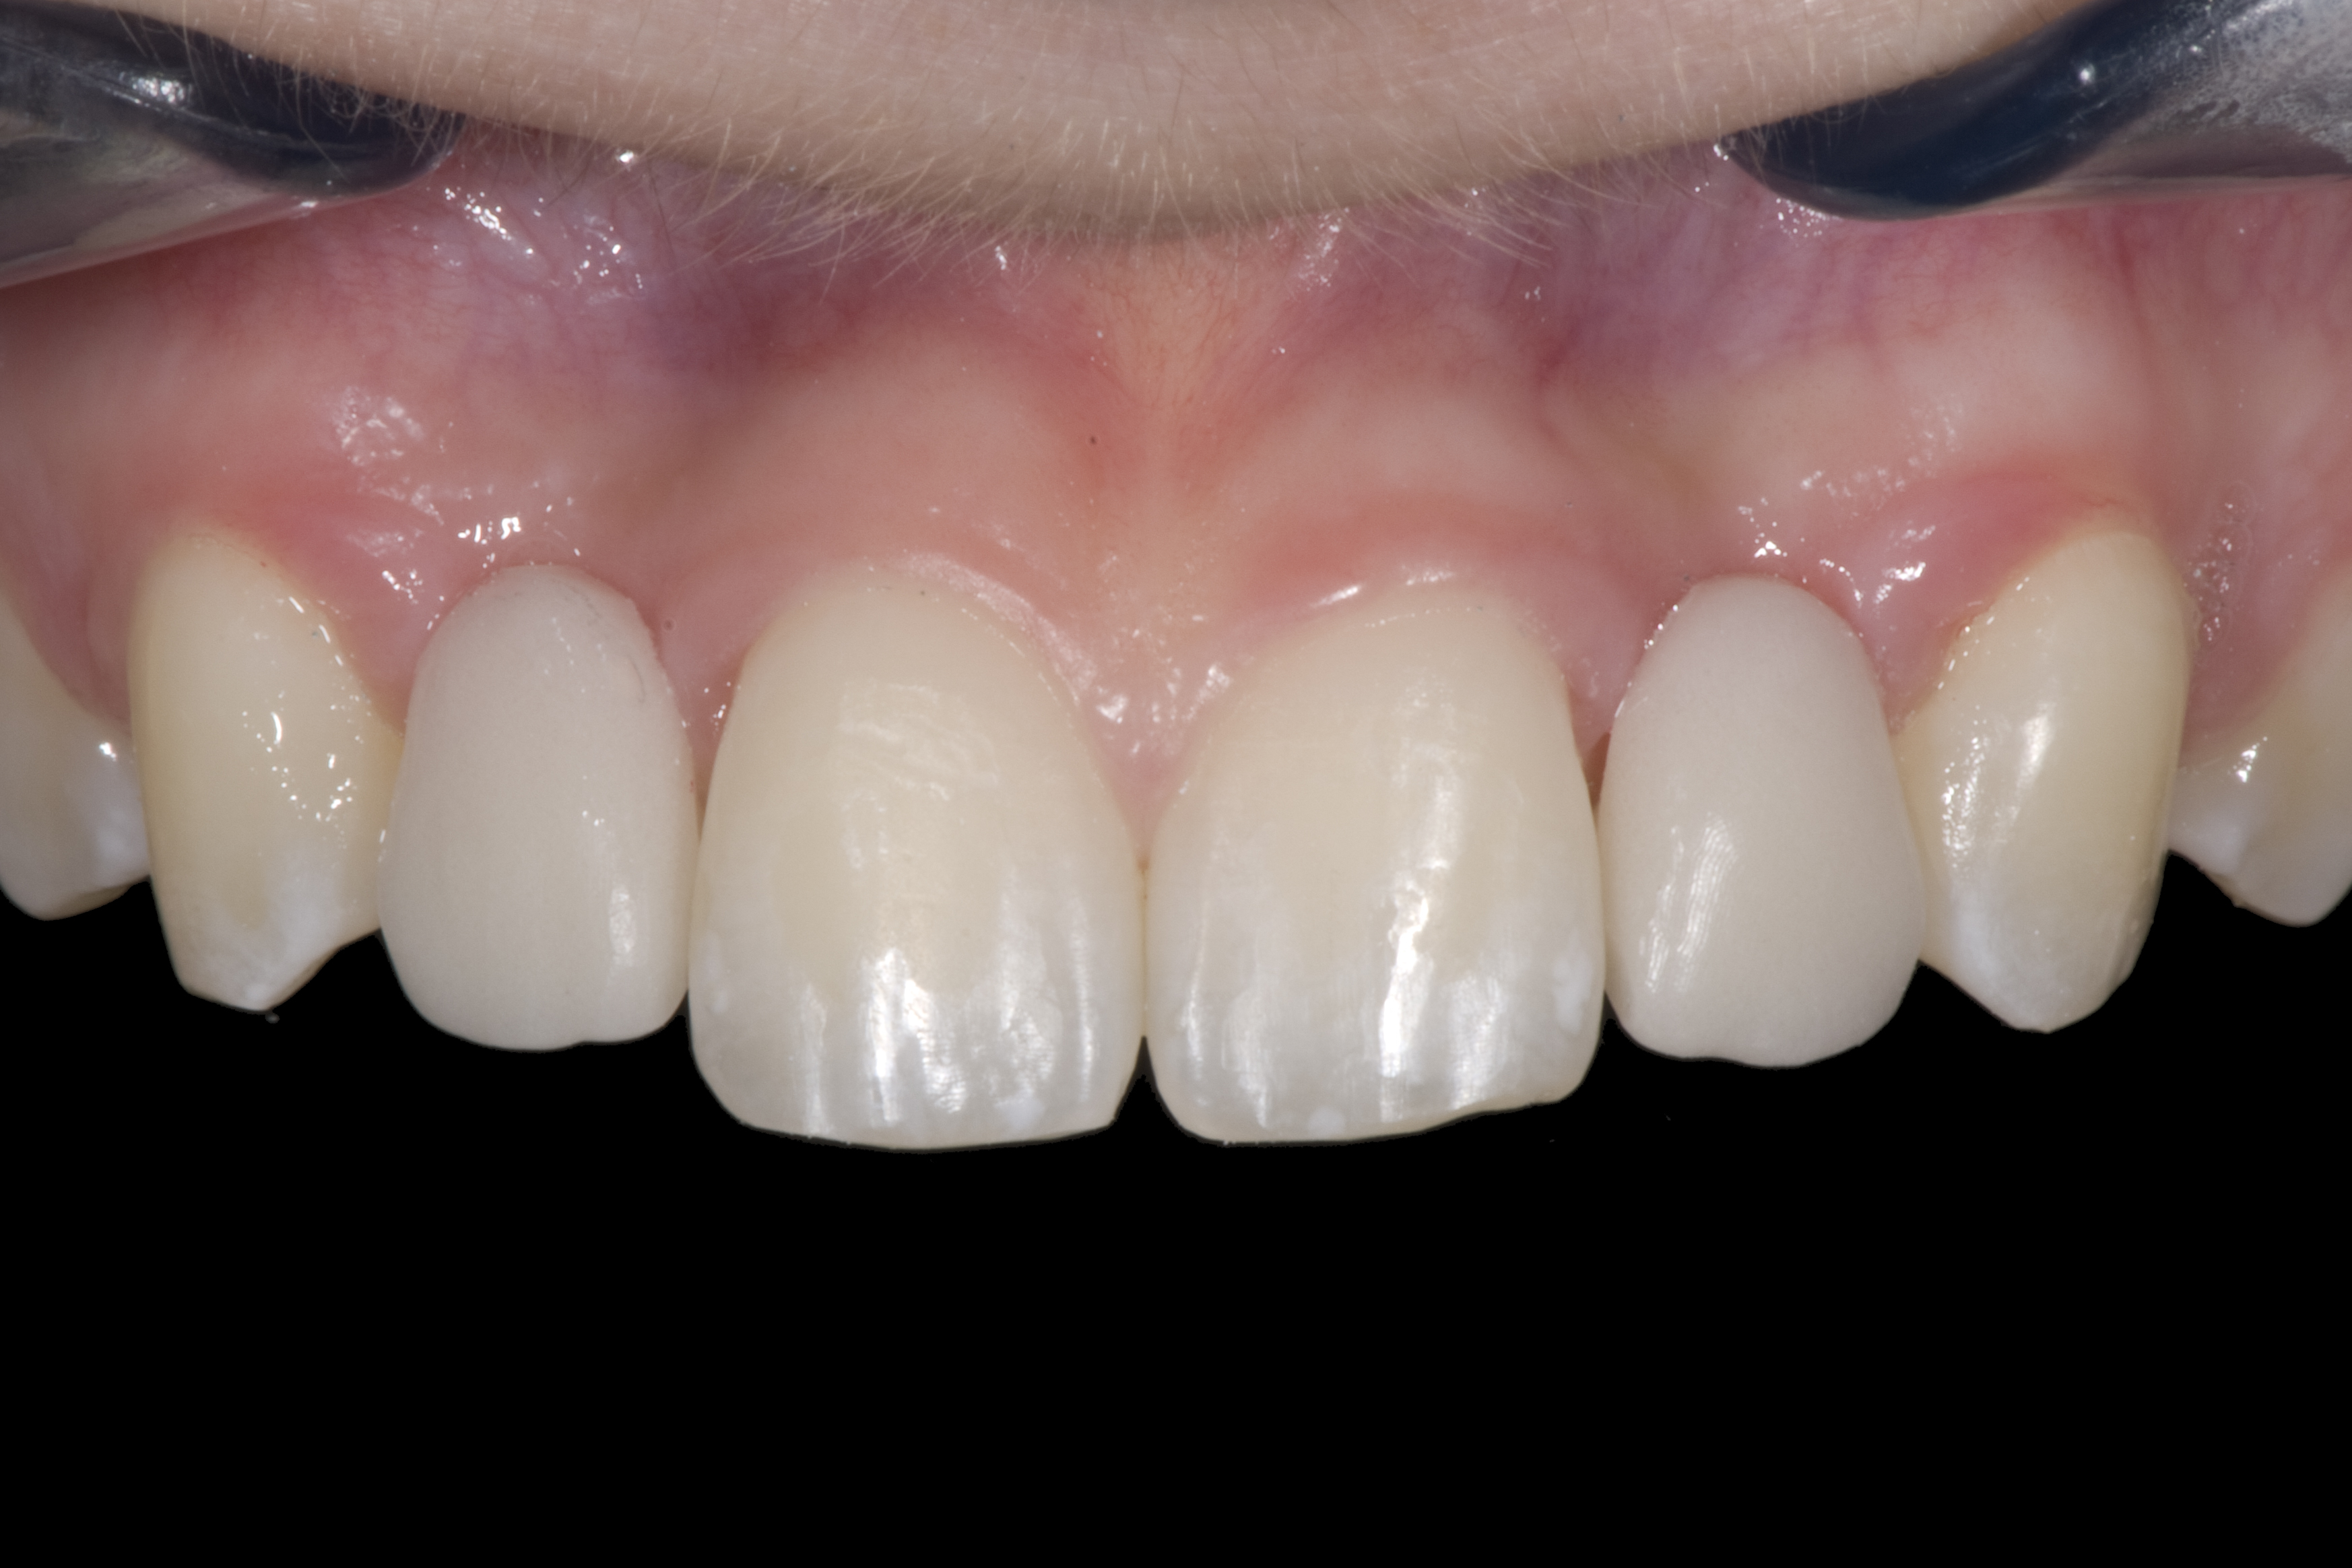

(20.) Facial view of final single-wing, modified zirconia resin-bonded bridges.

Figure 20

(21.) Smile view.

Figure 21

(22.) Right lateral view.

Figure 22

(23.) Left lateral view.

Figure 23

(24.) Occlusal view.

Figure 24

When the patient returned, the fit was evaluated in the mouth. Once verified, the internal surface of the framework was etched with a 9.5% hydrofluoric acid for 90 seconds and then salinized. After etching the enamel surface with phosphoric acid for 30 seconds and applying the primer (Single Bond Plus, 3M ESPE) to both the internal surface of the framework and the enamel, the zirconia bridge was bonded with a dual-cure resin cement (RelyX™ ARC, 3M ESPE). After the procedure, the patient ended up with a long-term, high-strength esthetic restoration advantaged by the bonding potential of fledspathic ceramic (Figure 20 through Figure 24). Six years after placement, the prosthesis had remained in place with no complications.